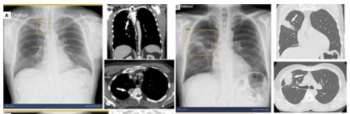

The AI-powered AZchest CXR software reportedly offers 93.79 percent sensitivity and a 98.57 percent AUC for pneumothorax.

Adjunctive use of the AI-powered software led to an average 38.6 percent increase in the detection of pneumothorax by general radiologists, according to a 2023 study.